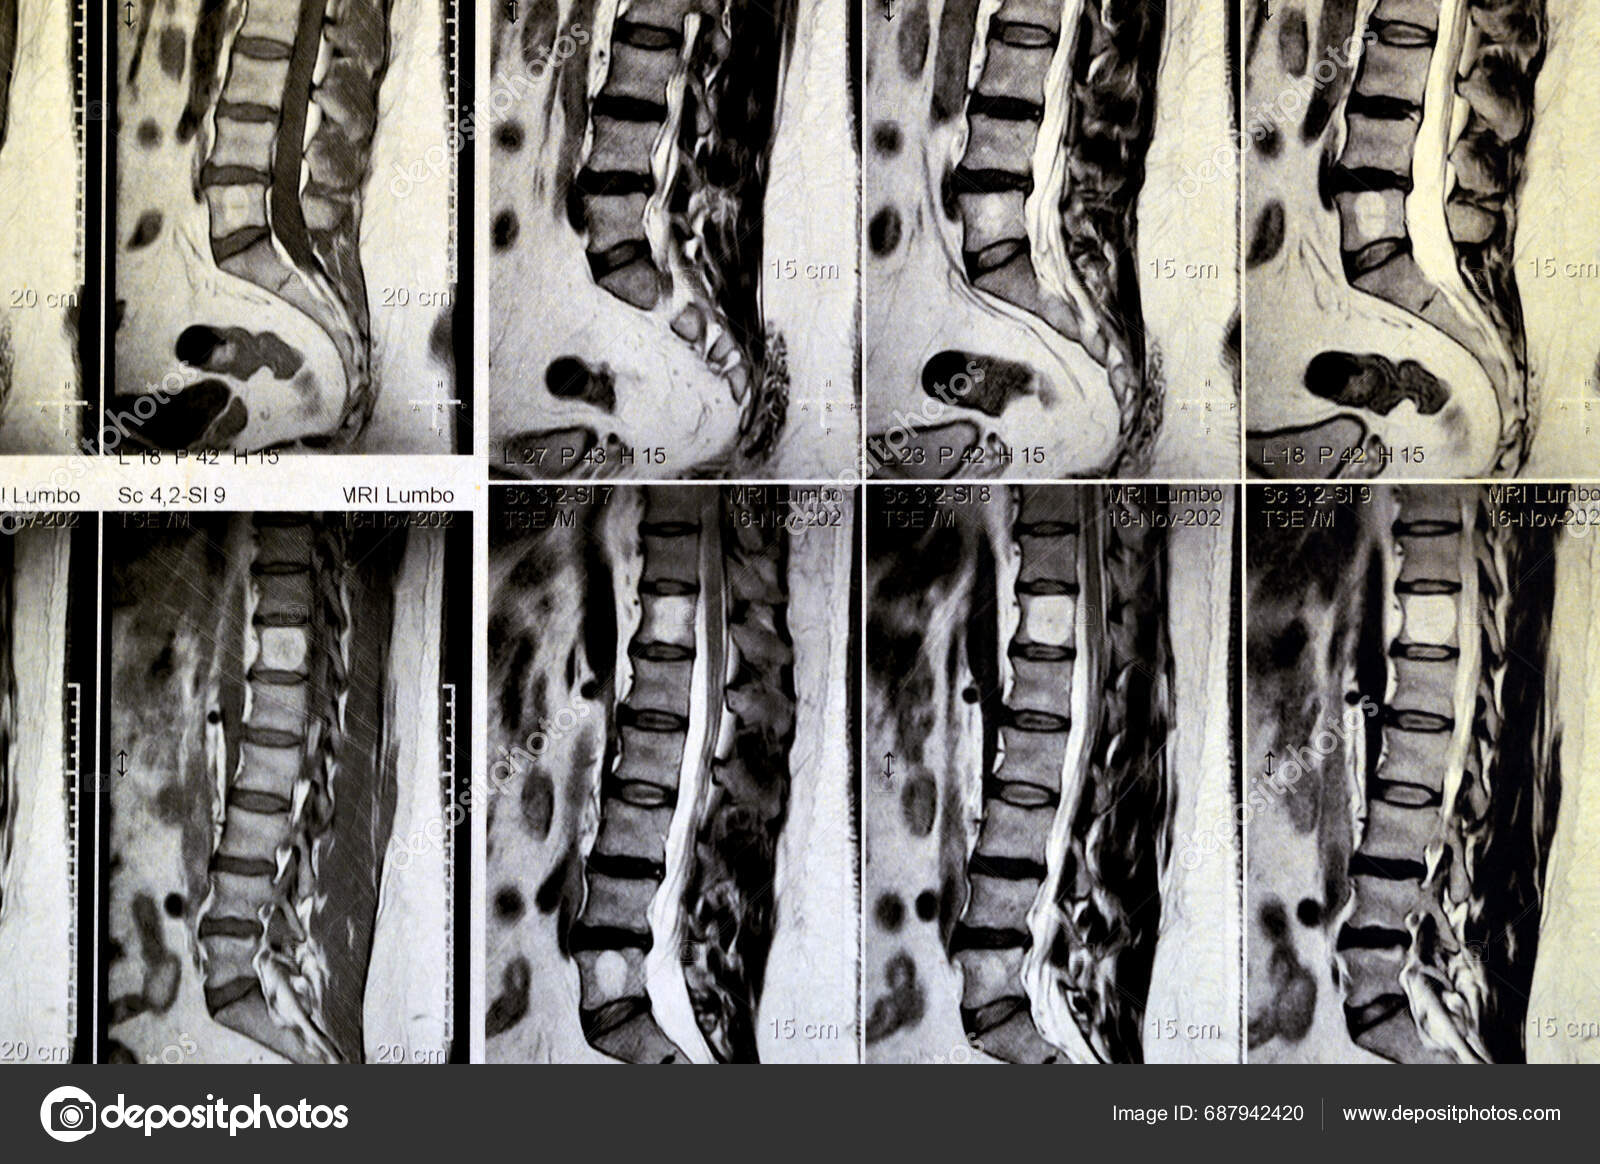

From depositphotos.com

Mri Lumbosacral Spine Contrast Revealed Back Muscle Spasm Mild Disc Lumbar Curvature Due To Muscle Spasm the most common symptom of lordosis is muscle pain. When your spine curves abnormally, your muscles get. there are three main types of spine curvature disorders, including: Prolonged or recurrent muscle spasms in the lower back can contribute to the. lordosis is the normal inward curvature of the spine in the lumbar region (lower back). A symptom. Lumbar Curvature Due To Muscle Spasm.